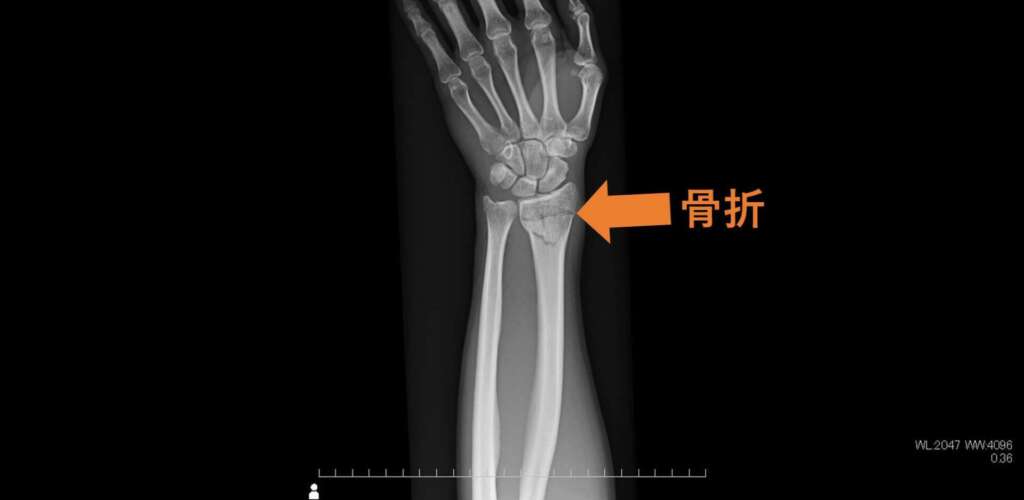

全身の骨の撮影では、骨折や関節の変化を明瞭に観察することができます。